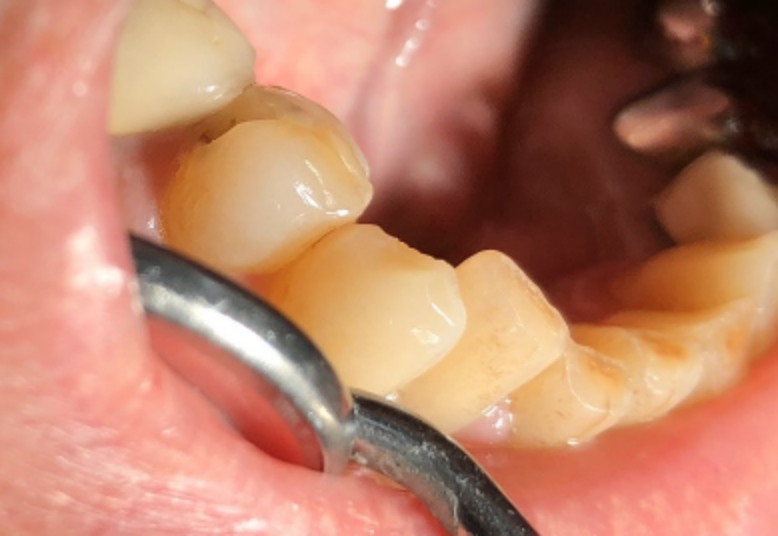

「王醫師,我中午吃便當時不小心咬到骨頭,突然間牙齒好痛,張口一看,牙齒被我咬斷了,我該怎麼辦?」A先生手裡拿著斷裂的那片牙齒,至北市聯醫仁愛院區牙科門診尋求協助,希望牙醫師能夠幫他把斷裂的碎片黏回,經過口內及影像檢查後,診斷為牙根垂直縱裂。牙醫師當下告知病人這顆牙齒無法保留,病人了解並且同意下決定當日拔除牙齒,解決了病人疼痛的問題。

王君翎解釋,假如牙齒斷裂位置已經從牙冠延伸到牙根,屬於比較嚴重的狀況,這類的牙齒大部分都必須拔除,以避免後續的發炎、腫脹。缺牙區域可考慮以固定式牙橋或人工植牙重建,恢復美觀及咀嚼功能。少部份斜裂到牙根的牙齒,斷裂位置靠近牙根頂端接近牙冠的部位,牙根有足夠長度,且牙周狀況良好,此時可考慮作牙冠增長術或局部牙齦切除,以利於日後假牙牙冠的製作。